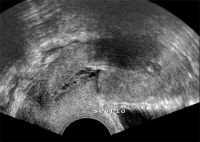

Tipps und Tricks im Gyn-Ultraschall: Die Sectionarbe am nichtschwangeren Uterus und in der Frühschwangerschaft

Journal für Gynäkologische Endokrinologie 2014; 8 (2) (Ausgabe für Österreich): 22-24 Journal für Gynäkologische Endokrinologie 2014; 8 (2) (Ausgabe für Schweiz): 24-26 Volltext (PDF) Abbildungen